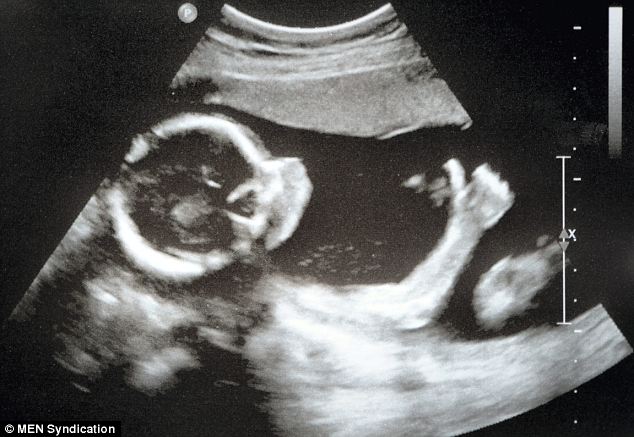

“Miracles Do Happen!” Premature Baby Born at 23 Weeks is Now Home November 11, 2025